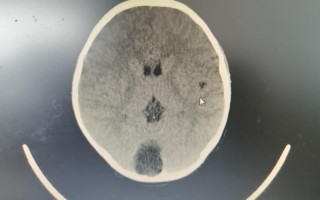

儿童健康 儿童蛛网膜囊肿症状有哪些? 绝大多数儿童蛛网膜囊肿是无症状的,通常是在因其他原因(如头部外伤、体检等)做影像学检查时偶然发现的,当囊肿确实引起症状时,其表现主要取决于囊肿的大小、位置以及是否对周围脑组织、颅骨或脑脊液循环造成了压... 99ANYc3cd6 2025-11-30 0 #儿童蛛网膜囊肿症状表现 #蛛网膜囊肿儿童常见症状 #蛛网膜囊肿对孩子的影响症状